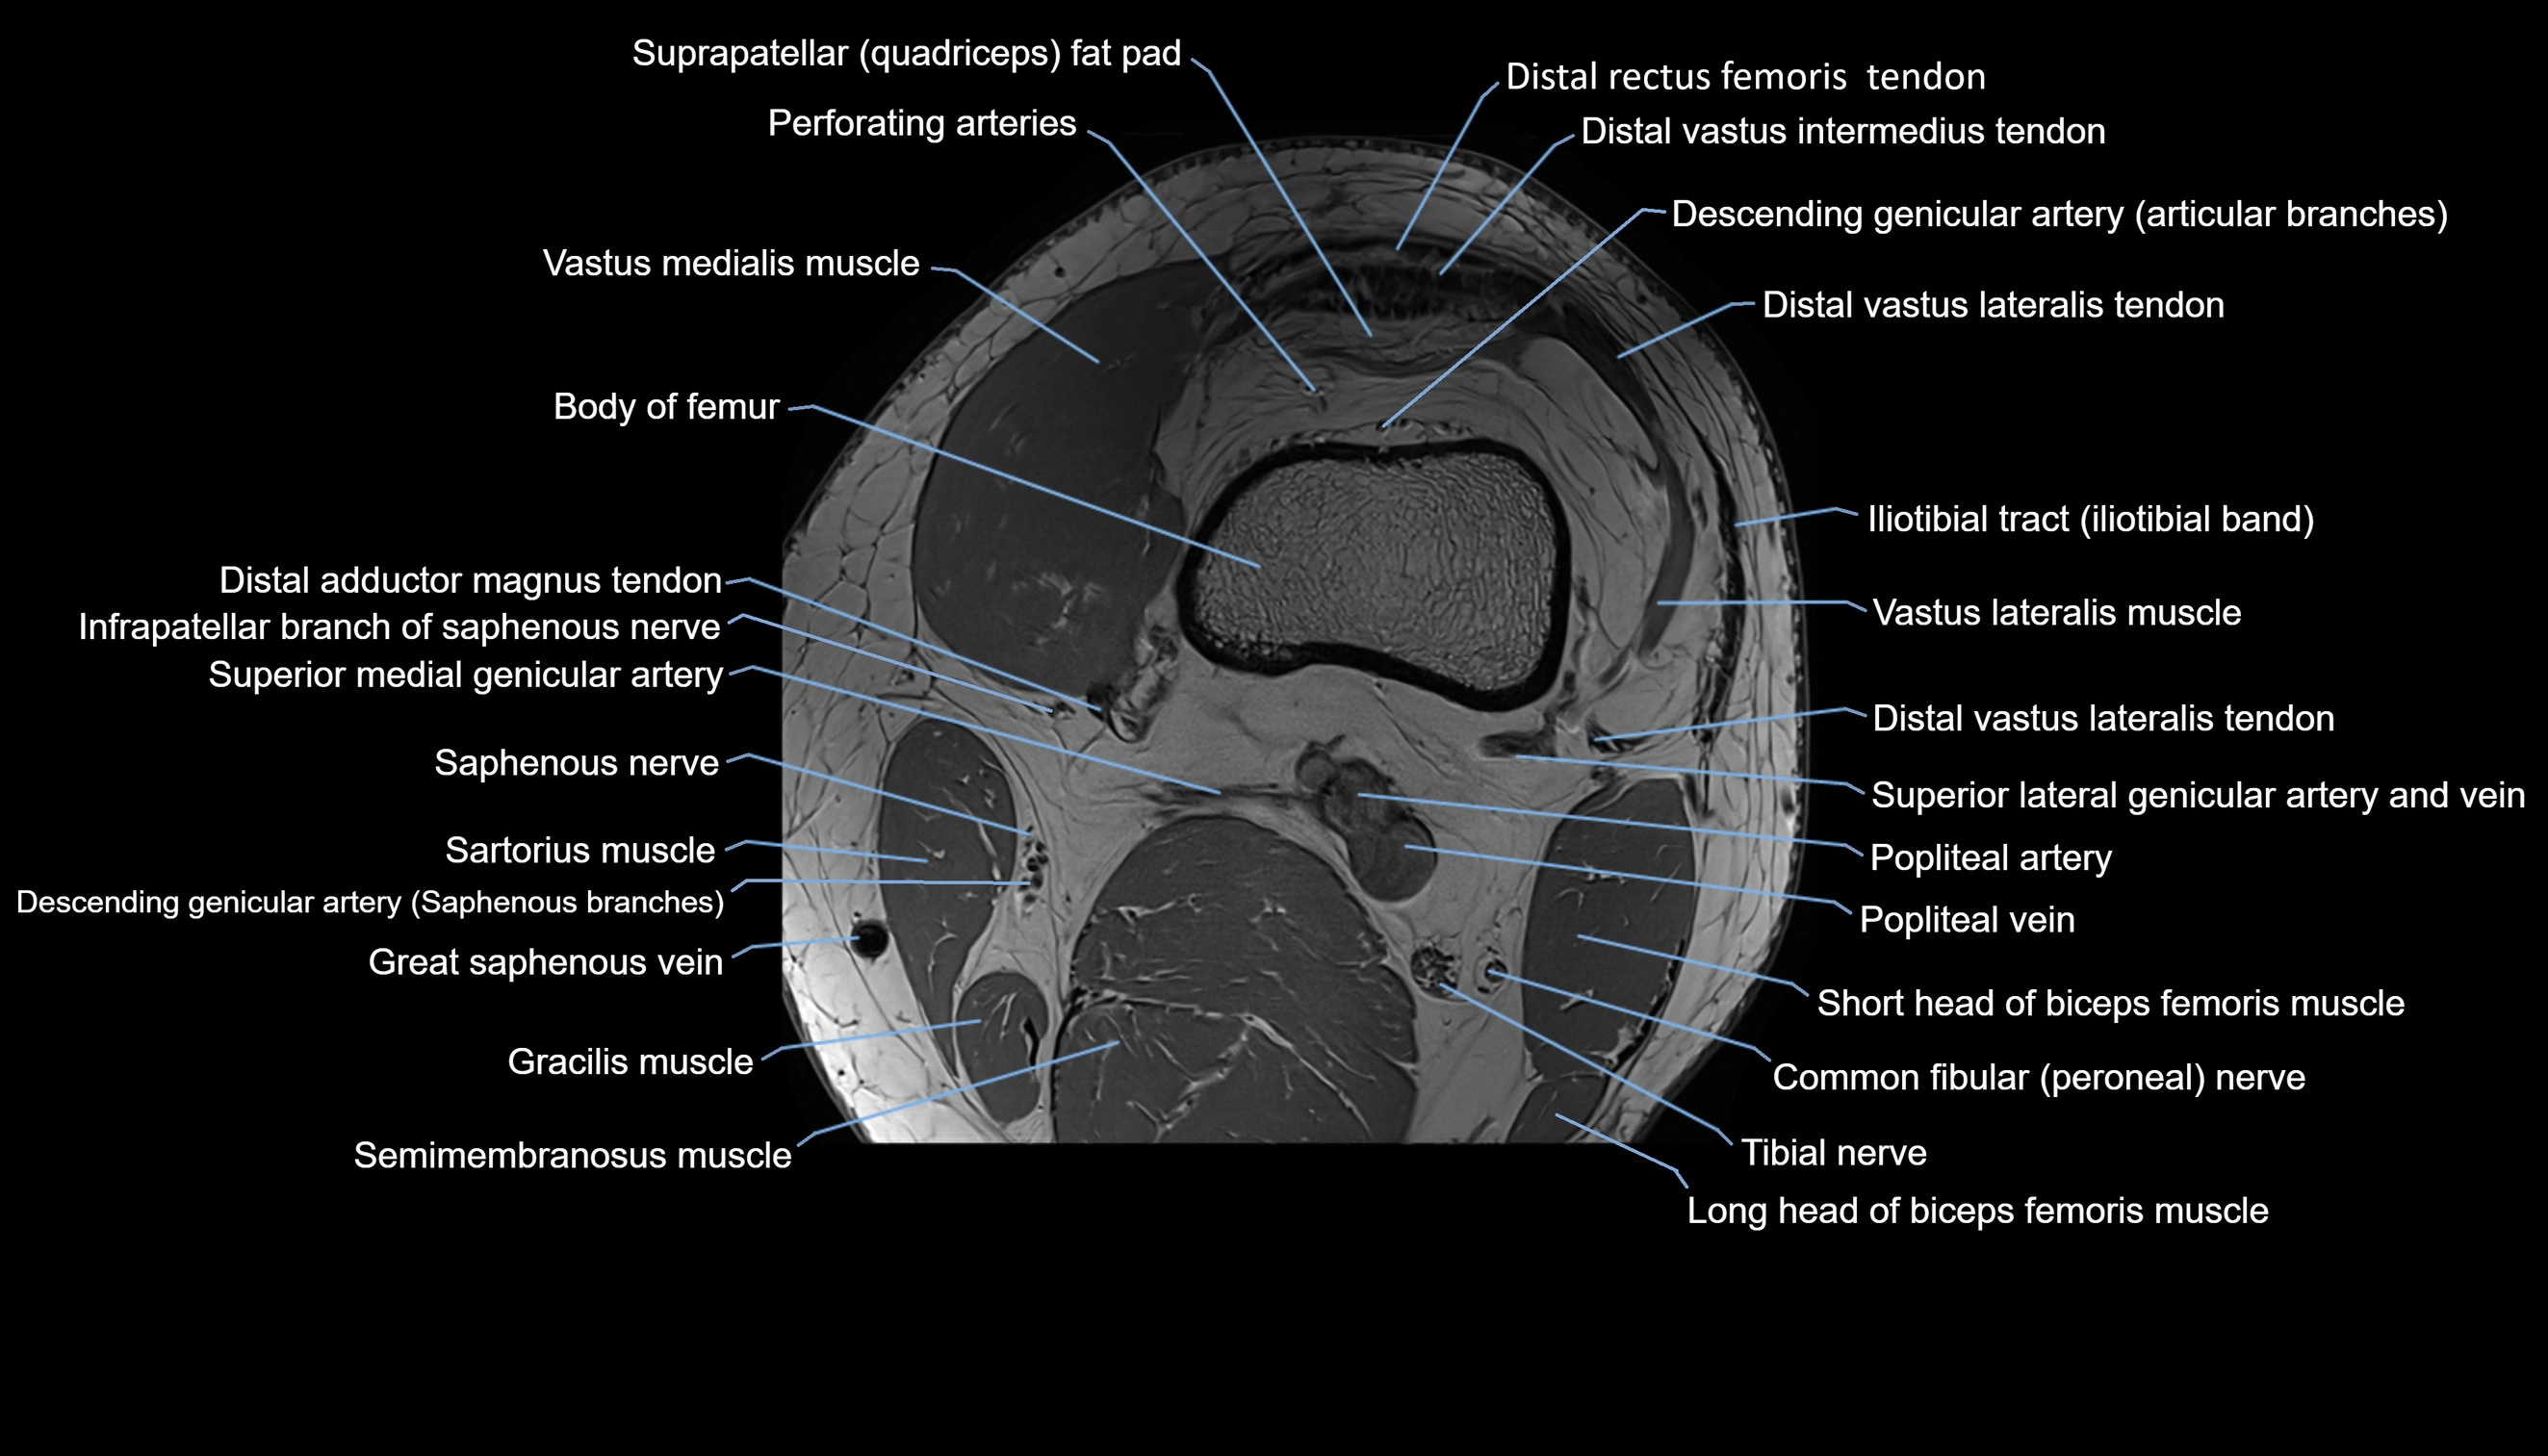

- Body of femur

- Distal rectus femoris tendon

- Distal vastus intermedius tendon

- Distal vastus lateralis tendon

- Descending genicular artery (Articular branches)

- Perforating Arteries (Knee joint)

- Prefemoral fat pad

- Suprapatellar fat pad

- Vastus lateralis muscle

- Vastus medialis muscle